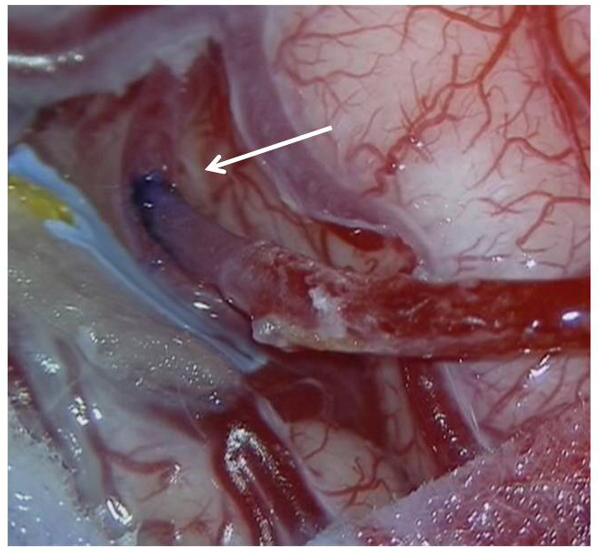

また脳梗塞の急性期は脳梗塞そのものに対する治療だけではなく脳梗塞に伴って起こってくる全身合併症の治療が重要です。麻痺のために身体を自由に動かすことができなくなったり食事をうまく摂ることができなくなるため栄養状態が悪くなりやすく肺炎を初めとする感染症が起こりやすくなります。全身の合併症は脳梗塞を更に悪化させその後の回復の可能性を低くしてしまうため早期から点滴や流動食などで栄養管理を行い、リハビリテーションで身体を動かしていただくようにします。脳の太い動脈が狭くなったり閉塞している場合には手術で狭窄部を広げたりバイパスを作って脳の血流を増やす治療が必要な時もあります。